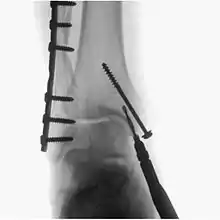

Fluoroscopy is used in various types of surgical procedure, such as orthopaedic surgery and podiatric surgery. In both of those, it is used to guide fracture reduction and in use in certain procedures that have extensive hardware.[6]